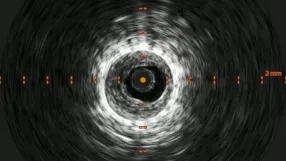

血管内超音波(IVUS)を行うとガイドワイヤーはステントの中心部を通過していたが、予想通り病変内には大量の血栓が堆積していた(動画4)。7 mmのバルーンで拡張したのち、ステント遠位端より2 cm程度離れた遠位の健常部にhealthy landingをとって(動画5)バイアバーン® ステントグラフト6 × 250 mmを留置した。近位側はステント近位端より1 cm程度離れたSFA入口部の健常部にhealthy landingをとって(動画6)バイアバーン® ステントグラフト7 × 150 mmを留置した。上下端とも既存のステントより外側にランディングをとること、ステントグラフトの電子添文の「使用上の注意」にあたる主要な側枝に注意して、大腿深動脈(DFA)や側副血行の流入部にかからないよう留意した。後拡張は血栓の上下方向へのprotrusionを防ぐ目的で先に遠位端、近位端の順に高圧バルーンで拡張し健常部血管壁への圧着をとった。ステントグラフトの中間部への後拡張はそのあとに続いて行った。最終造影で末梢まで塞栓がないことを確認して終了した(動画7)。